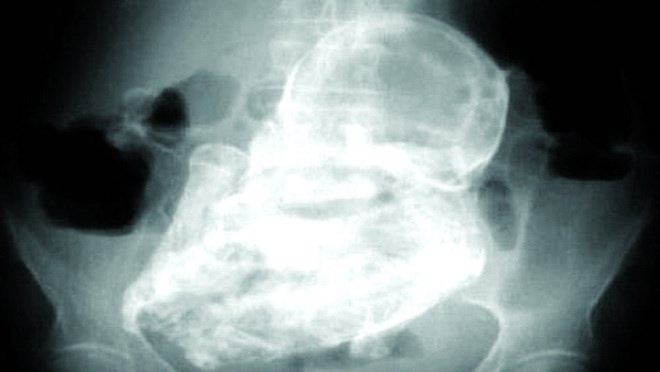

Bác sĩ phát hiện hộp sọ của bào thai đã vôi hóa 38 năm trong bụng một phụ nữ Ấn Độ, người mang bầu năm 1978 khi vừa tròn 24 tuổi.